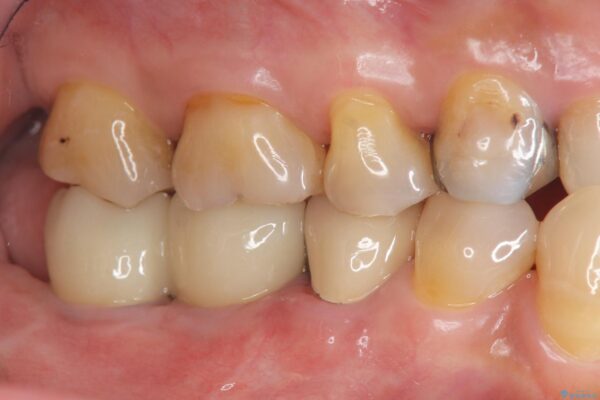

奥歯から膿のにおいがする インプラントによる機能回復 治療前画像 奥歯から膿のにおいがする インプラントによる機能回復 治療前画像 奥歯から膿のにおいがする インプラントによる機能回復 治療前画像 奥歯から膿のにおいがする インプラントによる機能回復 治療前画像 奥歯から膿のにおいがする インプラントによる機能回復 治療前画像 奥歯から膿のにおいがする インプラントによる機能回復 治療前画像

治療中

奥歯から膿のにおいがする インプラントによる機能回復 治療中画像 奥歯から膿のにおいがする インプラントによる機能回復 治療中画像 奥歯から膿のにおいがする インプラントによる機能回復 治療中画像 奥歯から膿のにおいがする インプラントによる機能回復 治療中画像

治療後

奥歯から膿のにおいがする インプラントによる機能回復 治療後画像 奥歯から膿のにおいがする インプラントによる機能回復 治療後画像 奥歯から膿のにおいがする インプラントによる機能回復 治療後画像 奥歯から膿のにおいがする インプラントによる機能回復 治療後画像